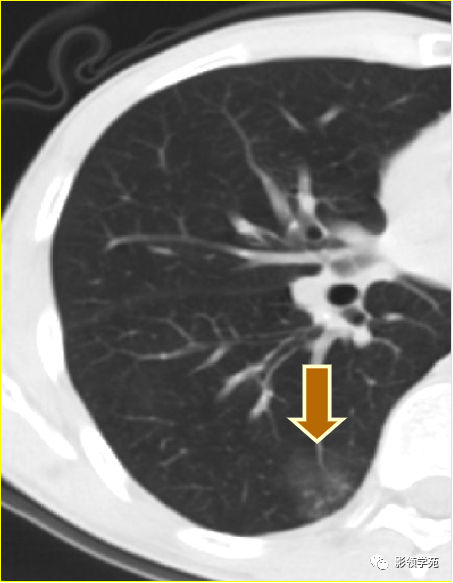

(2)空洞病变发生于双肺上叶尖后段、下叶背段,病变周围可见点状、结节状及片状卫星病灶,洞壁组织无明显强化或有包膜线样强化时,考虑结核;结核球的空洞多位于病变的肺门侧,与引流支气管相同,洞内壁一般较光滑。